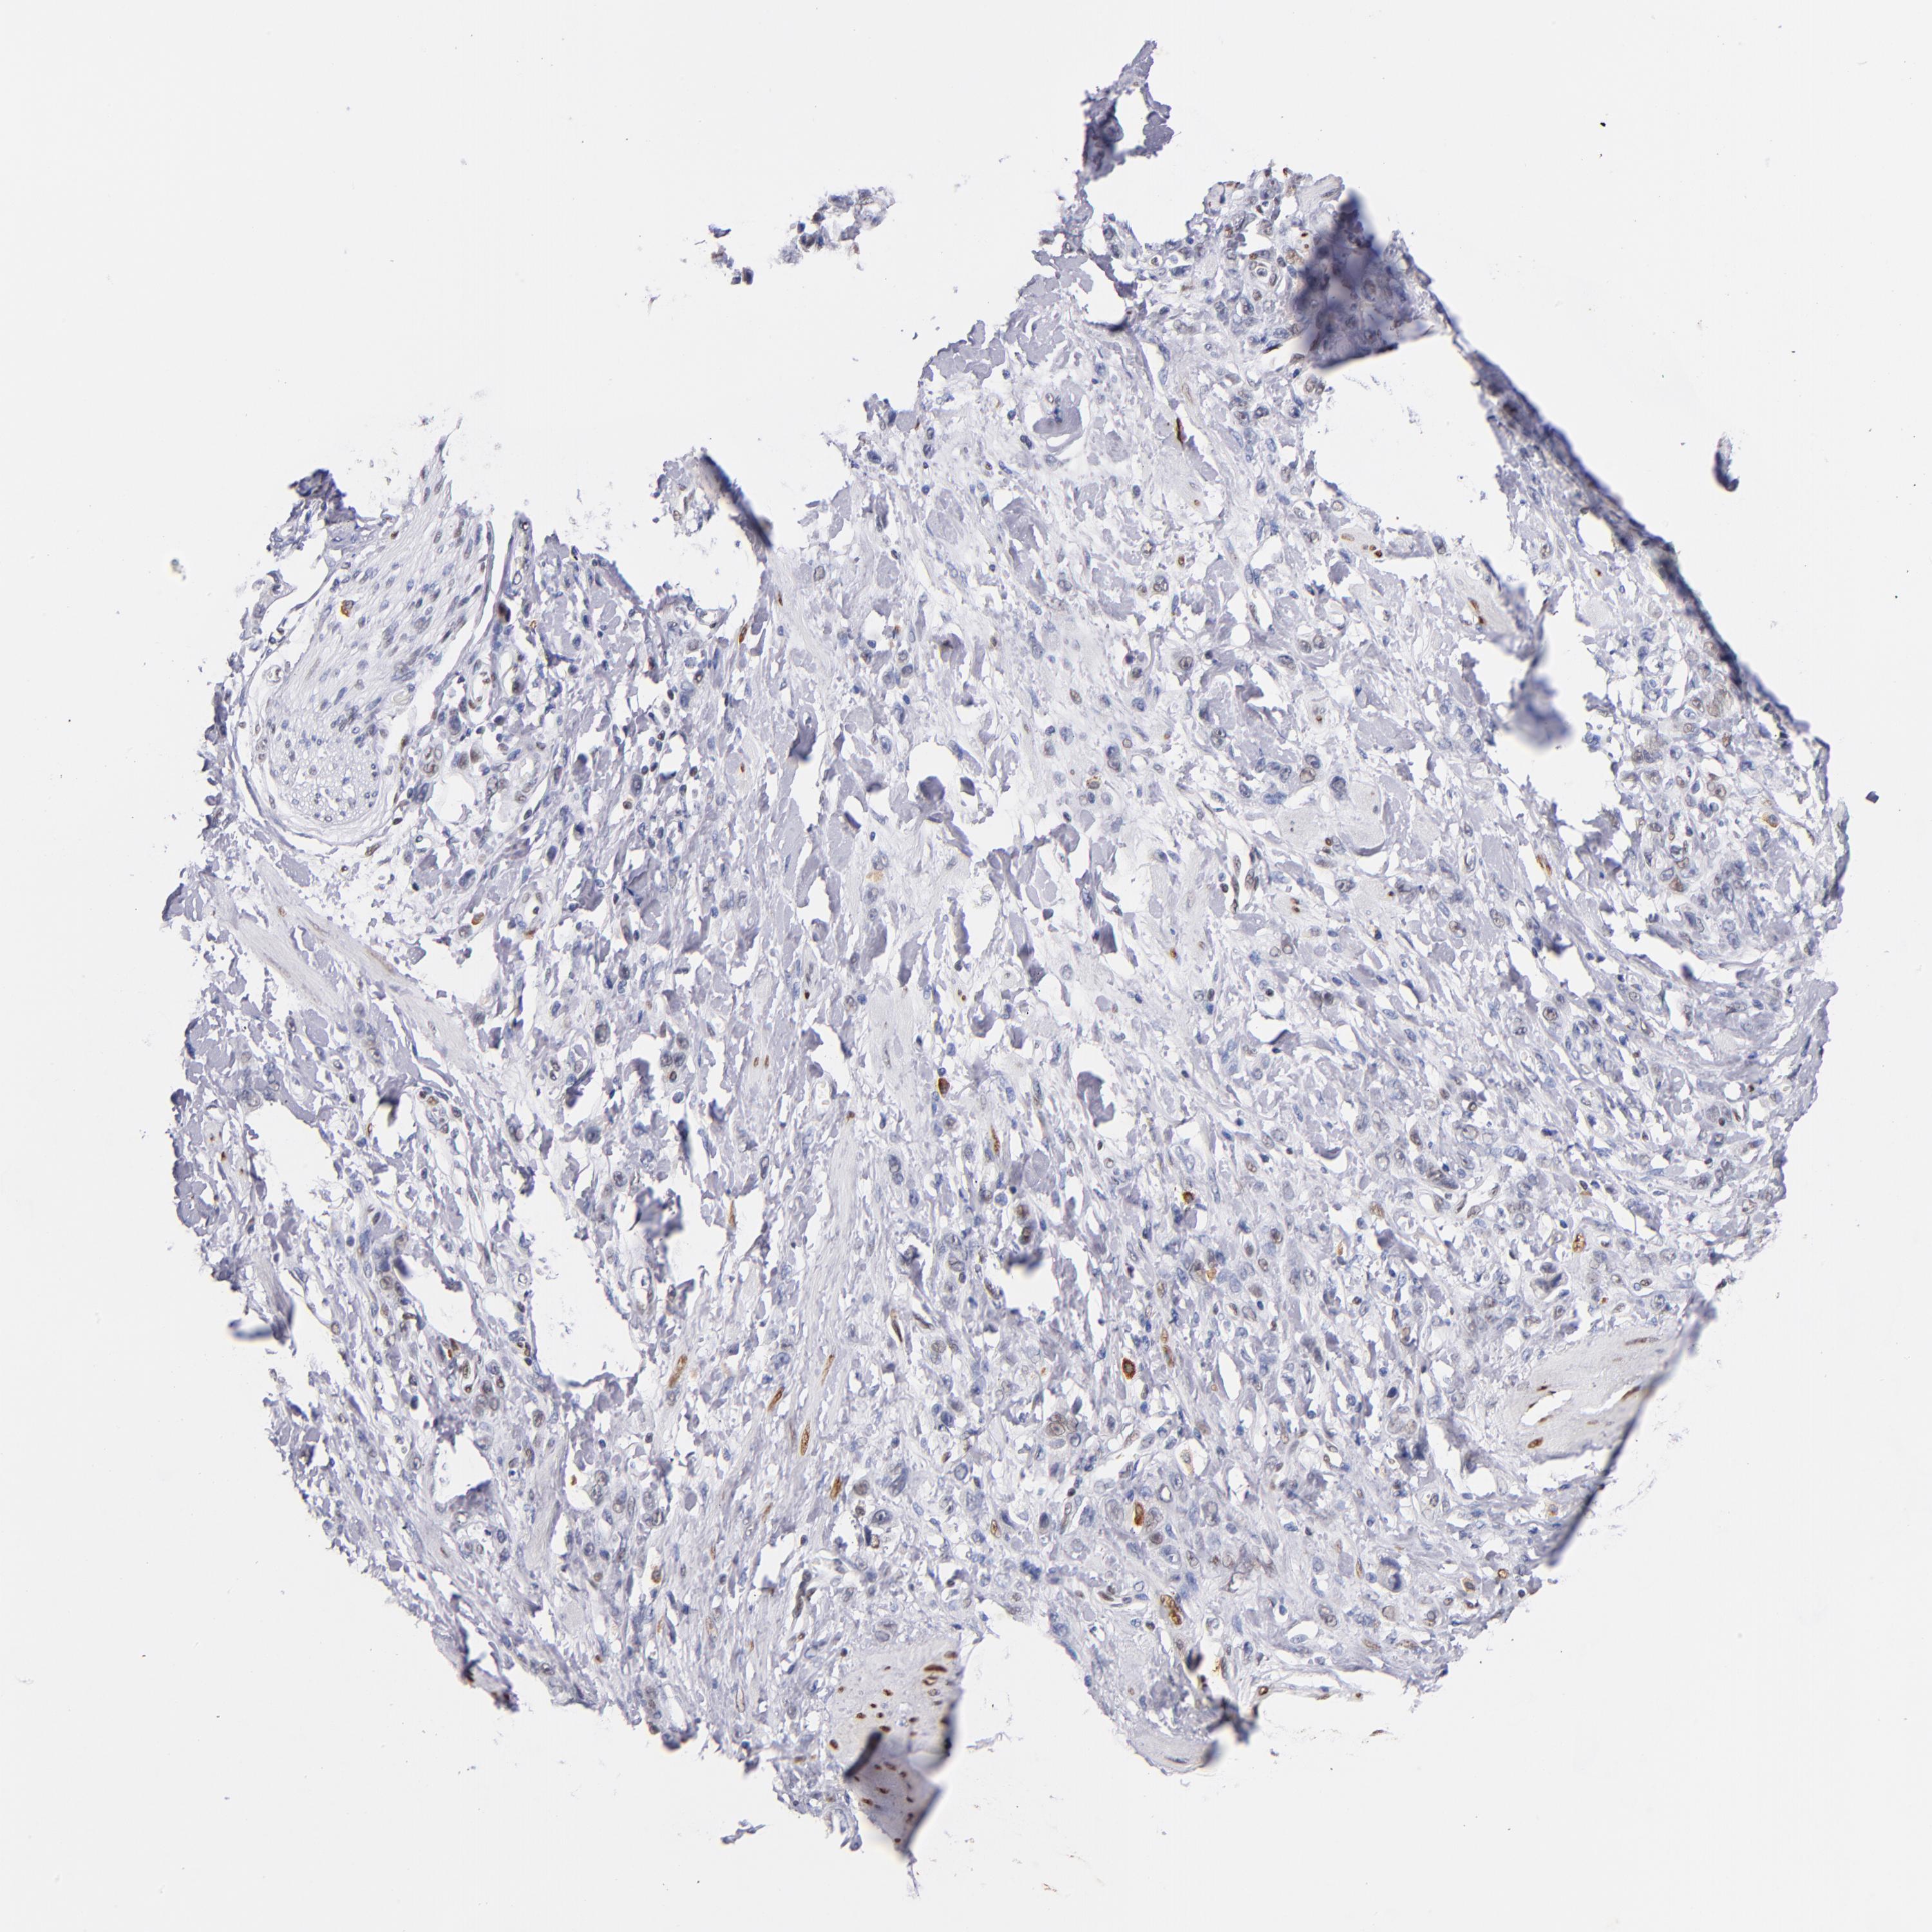

STOMACH CANCER - Protein expressioni

A mouse-over function shows sample information and annotation data. Click on an image to view it in a full screen mode. Samples can be filtered based on level of antibody staining by selecting one or several of the following categories: high, medium, low and not detected. The assay and annotation is described here.

Note that samples used for immunohistochemistry by the Human Protein Atlas do not correspond to samples in the TCGA dataset.

Antibody stainingi

Antibody staining in the annotated cell types in the current human tissue is reported as not detected, low, medium, or high, based on conventional immunohistochemistry profiling in selected tissues. This score is based on the combination of the staining intensity and fraction of stained cells.

Each image is clickable and will lead to virtual microscopy that enables deeper exploration of all samples and also displays staining intensity scores, fraction scores and subcellular localization as well as patient and tissue information for each sample.

Antibody HPA001819

Antibody CAB005416

Staining

High

Medium

Low

Not detected

Intensity

Strong

Moderate

Weak

Negative

Quantity

>75%

75%-25%

<25%

None

Location

Nuclear

Cytoplasmic/membranous

Cytoplasmic/membranous,nuclear

Adenocarcinoma, NOS

Adenocarcinoma, High grade